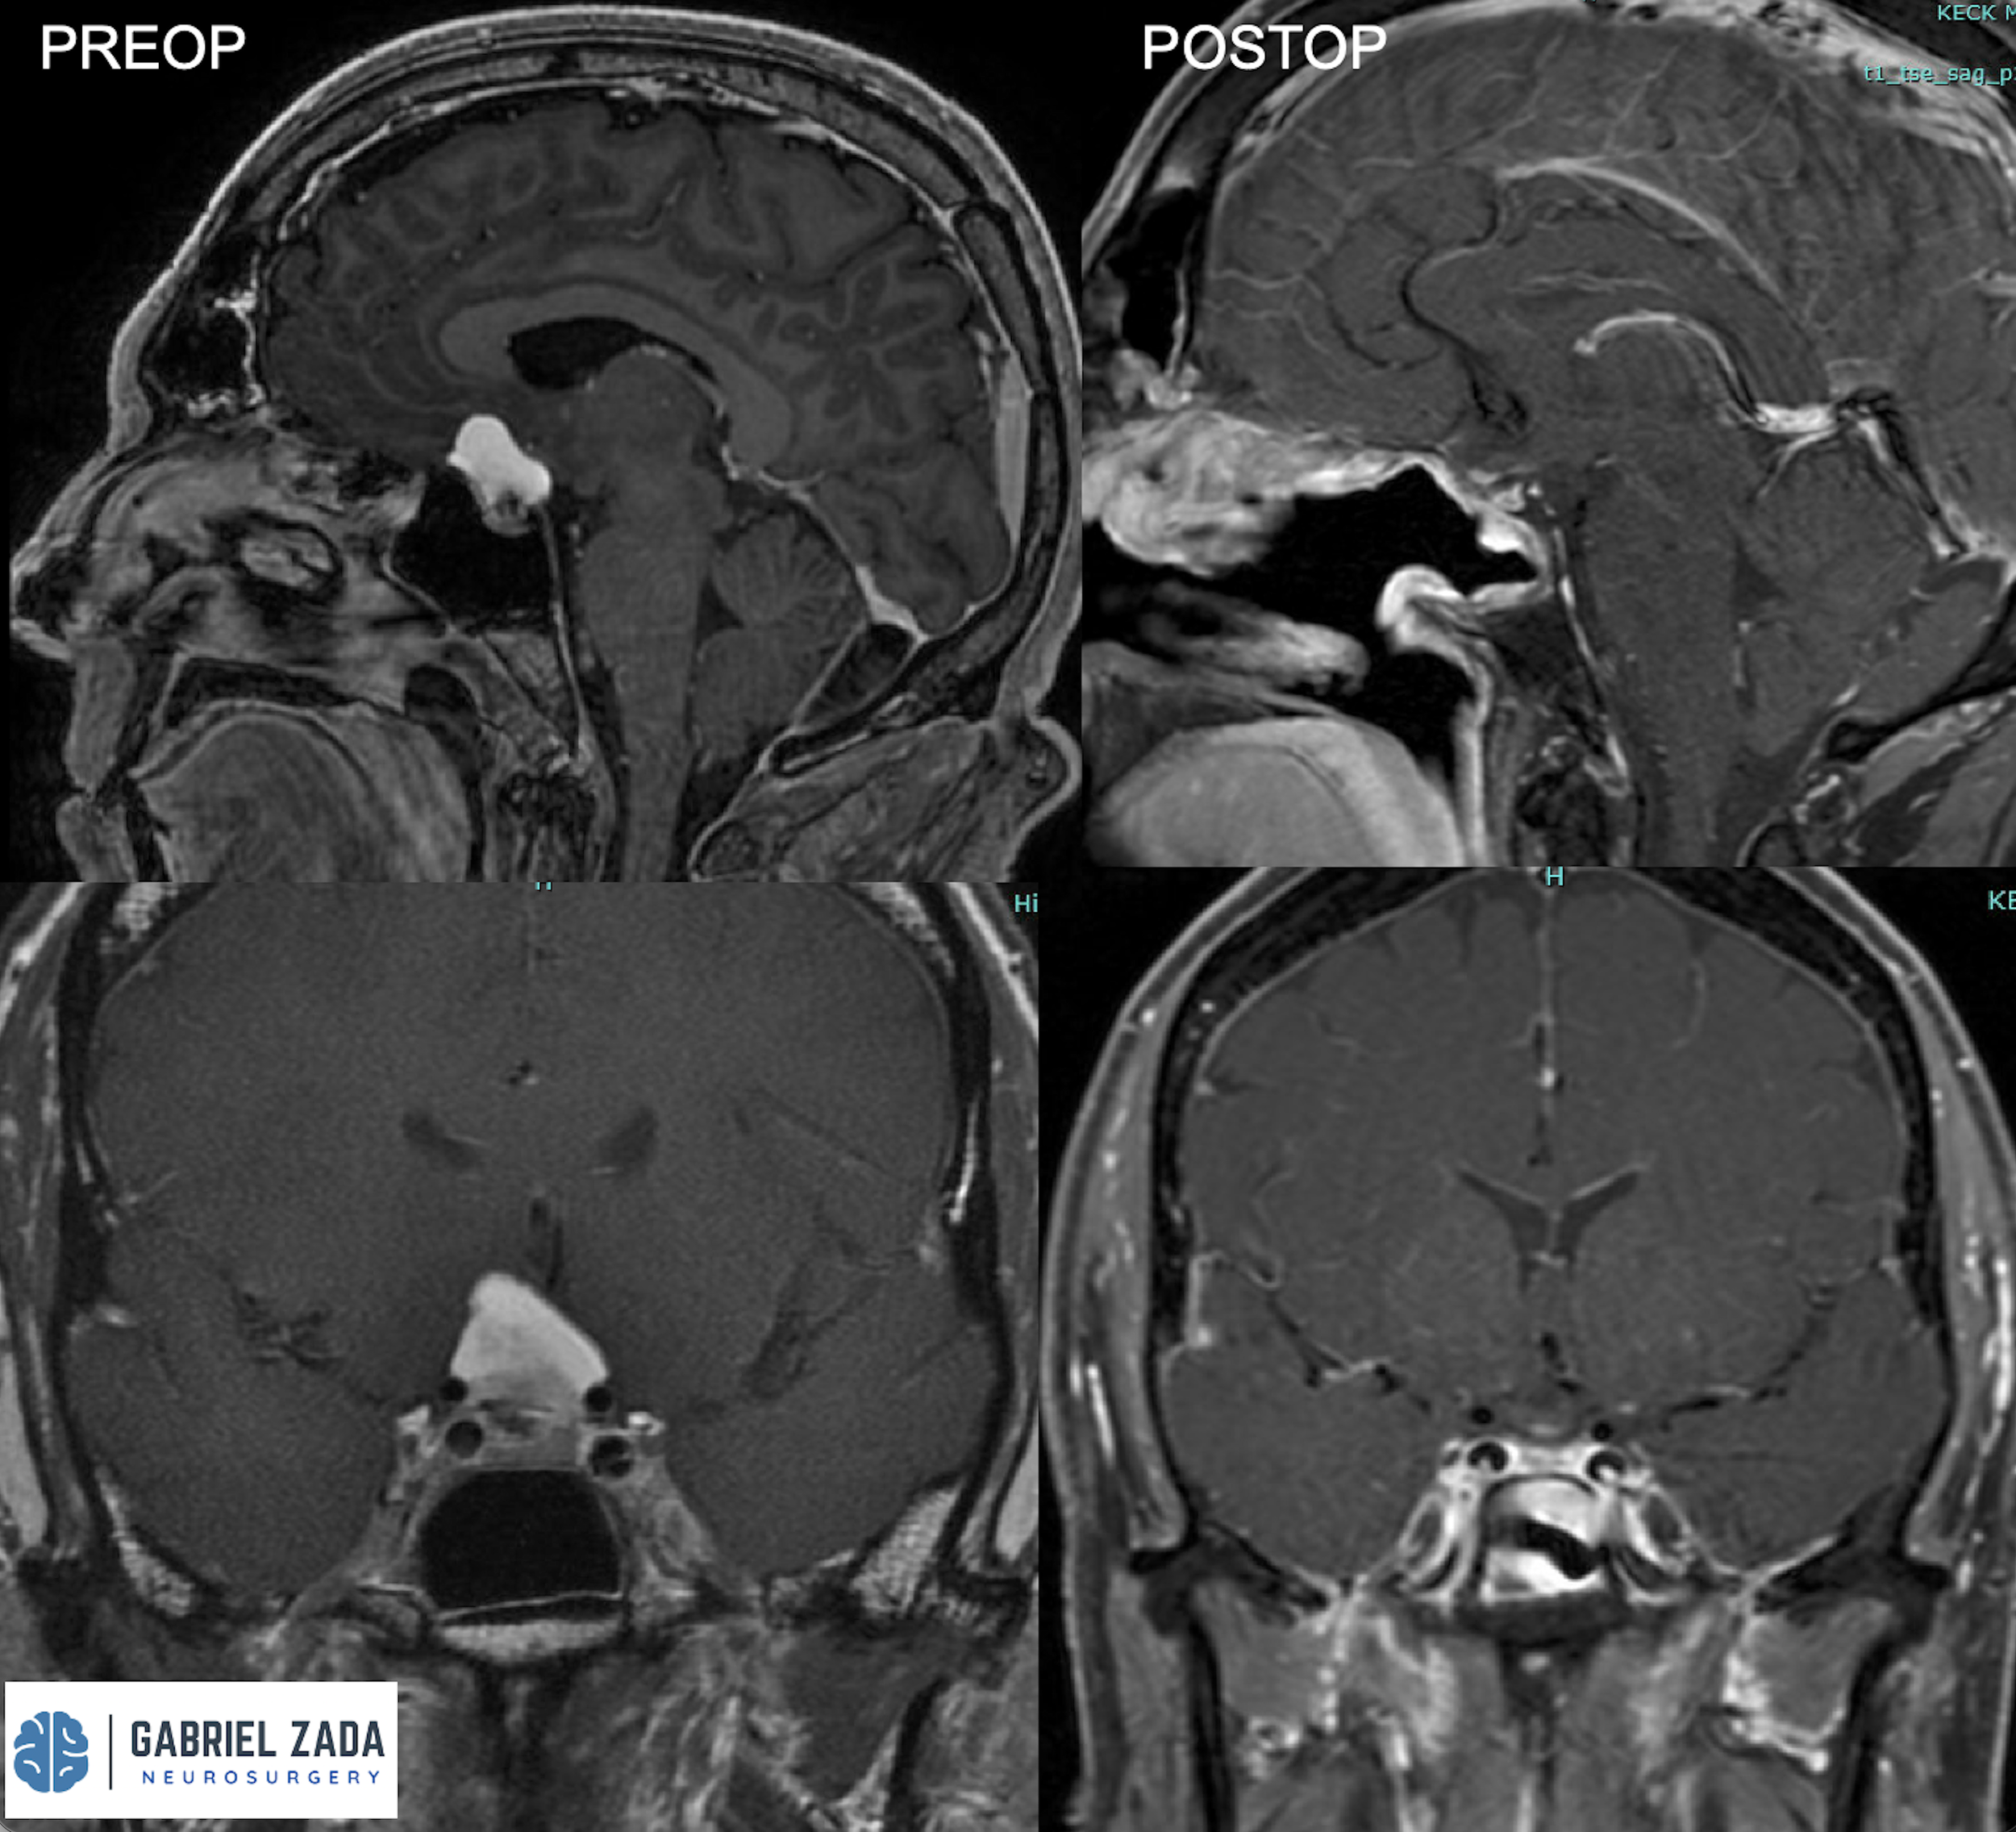

Explore this comprehensive gallery featuring pre‑ and post‑operative imaging of patients with skull‑base tumors treated by Gabriel Zada, MD, MS, FAANS, FACS. These cases highlight Dr. Zada’s expertise in advanced neurosurgical techniques and outcomes.

*Representative cases shown for educational purposes. All images de-identified. Individual results vary.